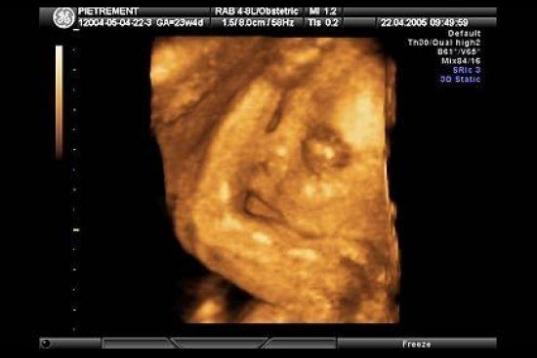

En esta galería puedes ver en fotos como es el desarrollo de un feto de semana en semana:

Desarrollo del feto, en fotos